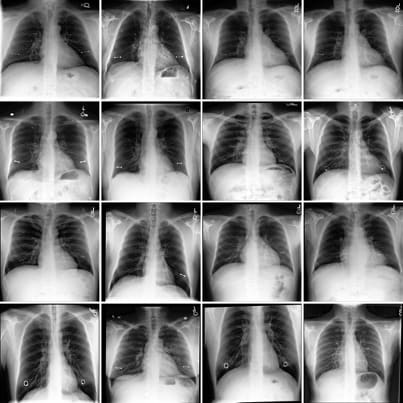

We train Sparse Autoencoders (SAEs) on the class token of a radiology image encoder, on a dataset of chest x-rays. We use the trained SAE, in conjunction with automated interpretability, to generate radiology reports. The final radiology report represents a concatenation of the text descriptions of activate SAE features. We train a diffusion model to allow causal interventions on SAE features. This diffusion model enables us to highlight where in the chest x-ray each sentence in the radiology report comes from by localising changes in the image post-intervention. Our method achieves competitive accuracy in comparison to state of the art medical foundation models while using a fraction of the parameter count and compute costs. To the best of our knowledge, this is the first time SAEs have been used for a non-trivial downstream task - namely to perform multi-modal reasoning on medical images.

Of particular note to the mechanistic interpretability community, we demonstrate that SAEs extract sparse and interpretable features on a small dataset (240,000) of homogenous images (chest x-rays appear very homogenous), and that these features can be accurately labeled by means of automated interpretability to produce pathologically relevant findings.